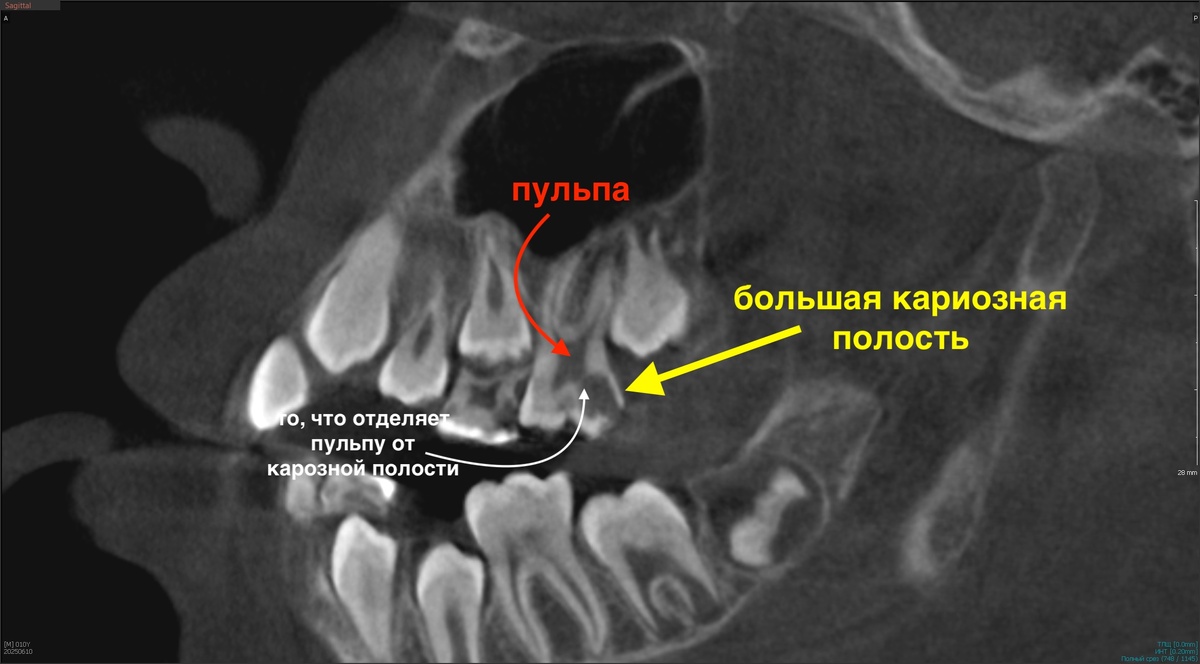

На КТ всё выглядит плохо:

Видите, насколько тонкая полоска твёрдых тканей отделяет пульпу от краха? Приблизим:

Пульпит?

Доктор почти уверен, что придётся лечить пульпит - делать эндодонтию.

Проводит чёткое диагностическое мероприятие, называемое фриз-тест.

Фриз-тест кратковременно положительный и быстропроходящий - признак живой, здоровой пульпы. Удивительно.